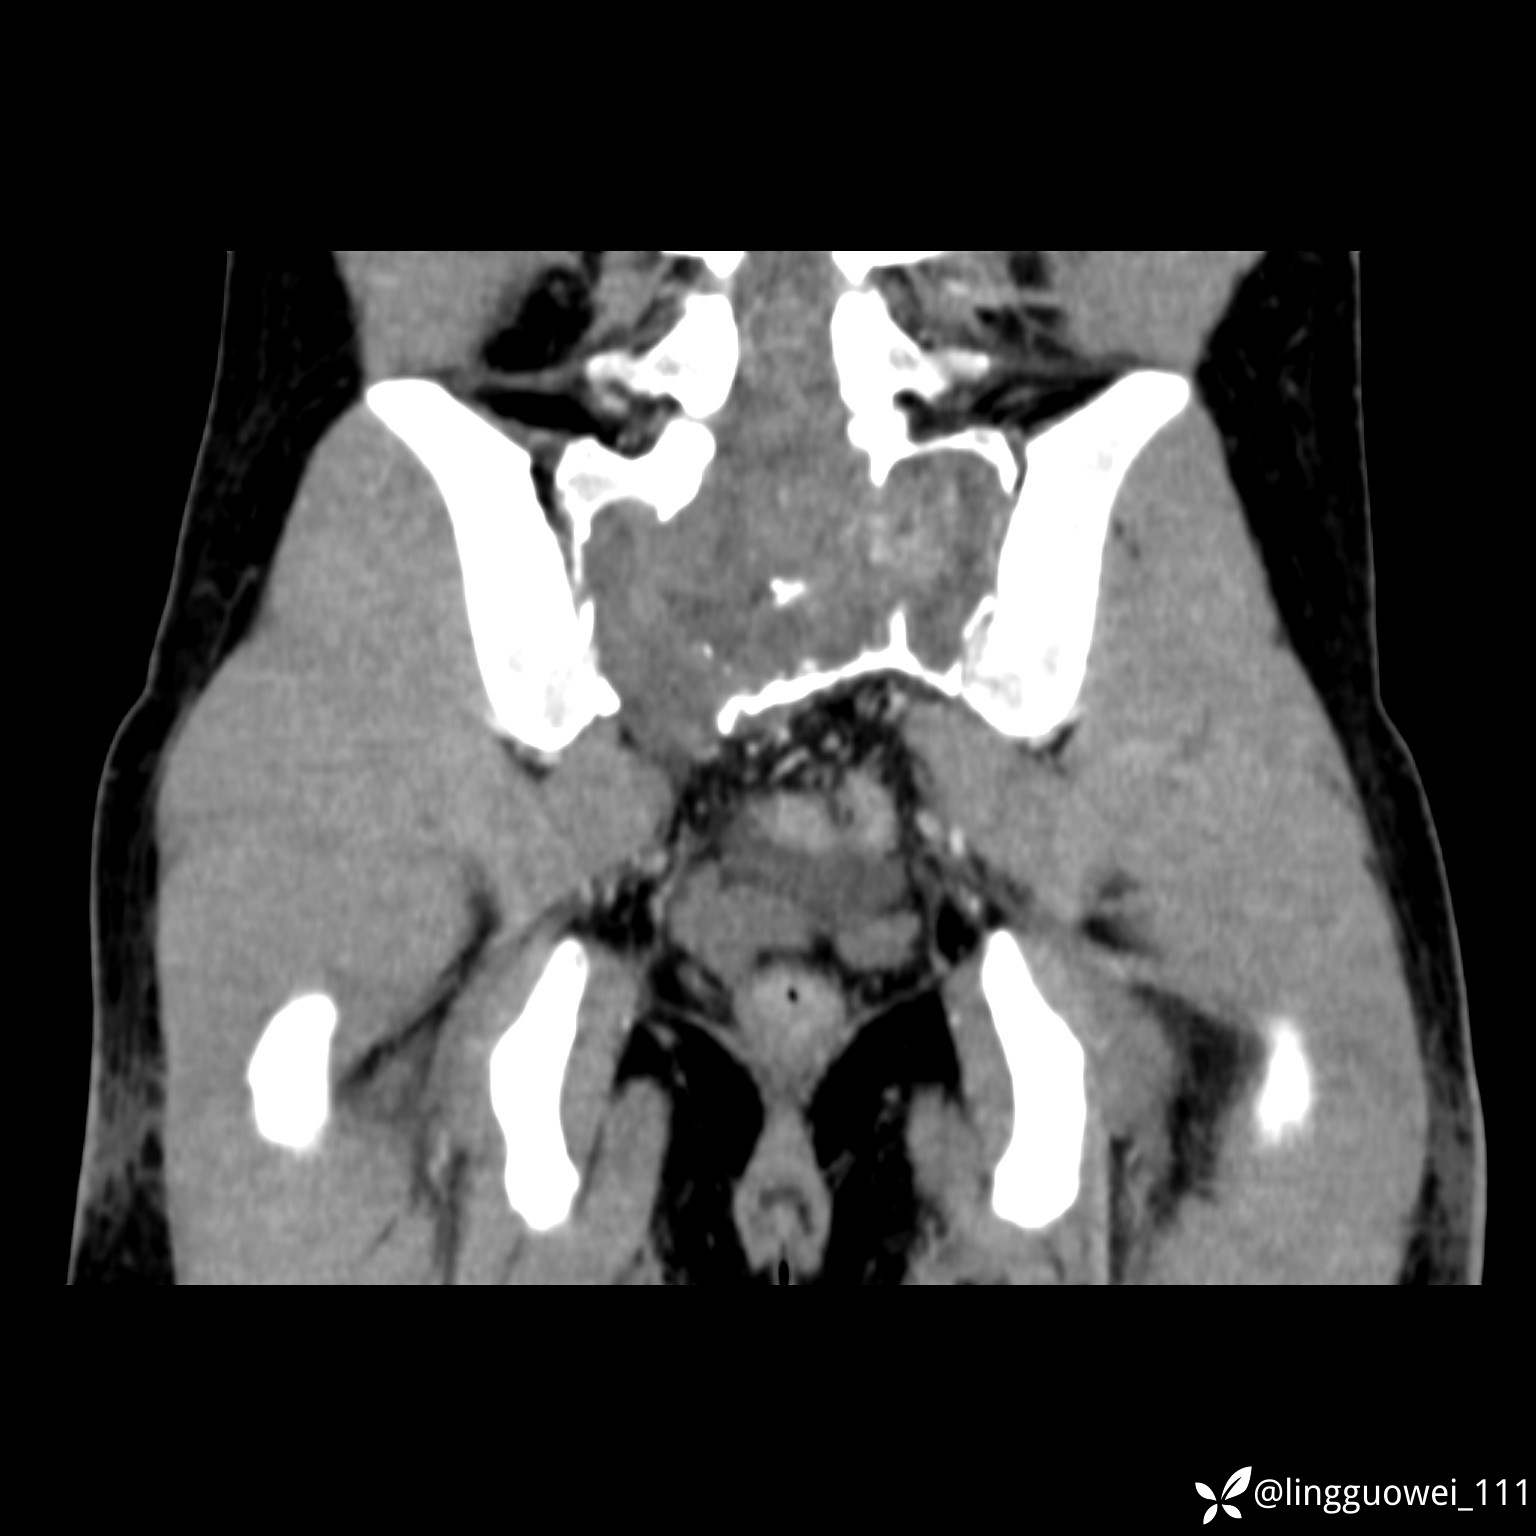

男,25岁,腰痛4年,加重左下肢痛5天,先上传X光片,第2天再上传CT。MR

静脉期:

img